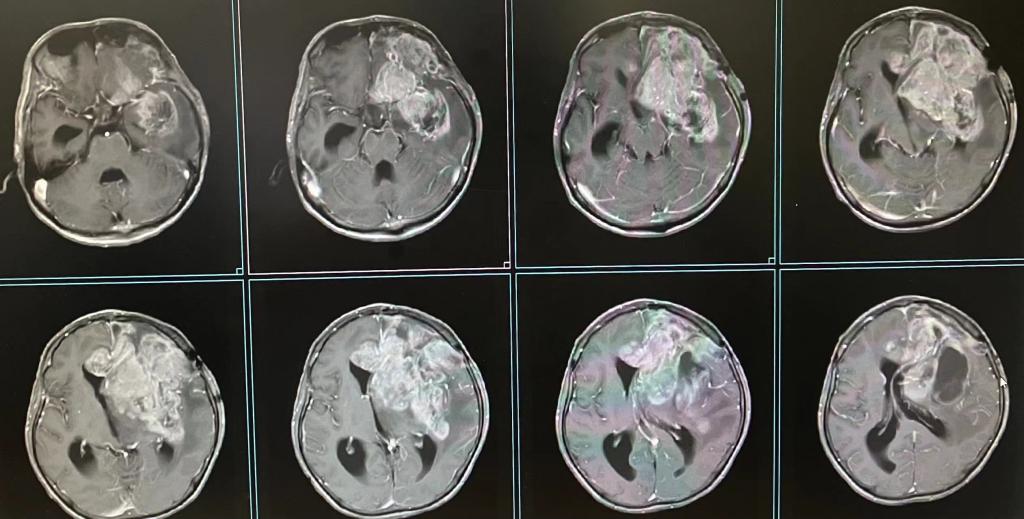

患者术前头颅MRI

经过营养支持等术前准备,在李松年主任的指导下,由池超超副主任医师主刀,周元鼓副主任医师为助手,为患者进行了开颅左侧大脑半球肿瘤切除术。术中探查见左侧额颞叶、基底节区、胼胝体见实质性肿物,呈灰红色鱼肉样,质韧,边界不清,肿瘤血供极其丰富,周围脑组织水肿明显,符合高级别胶质瘤表现。由于肿瘤复发累计范围更大,本次手术持续了10个小时,较为彻底地切除了复发的肿瘤。